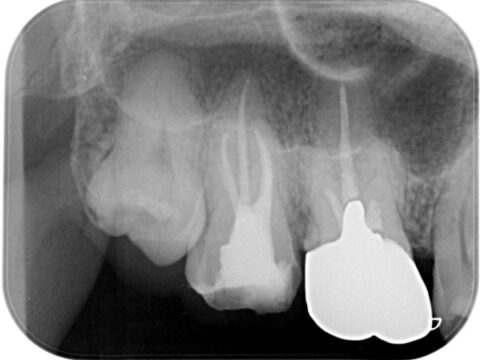

260226-001a